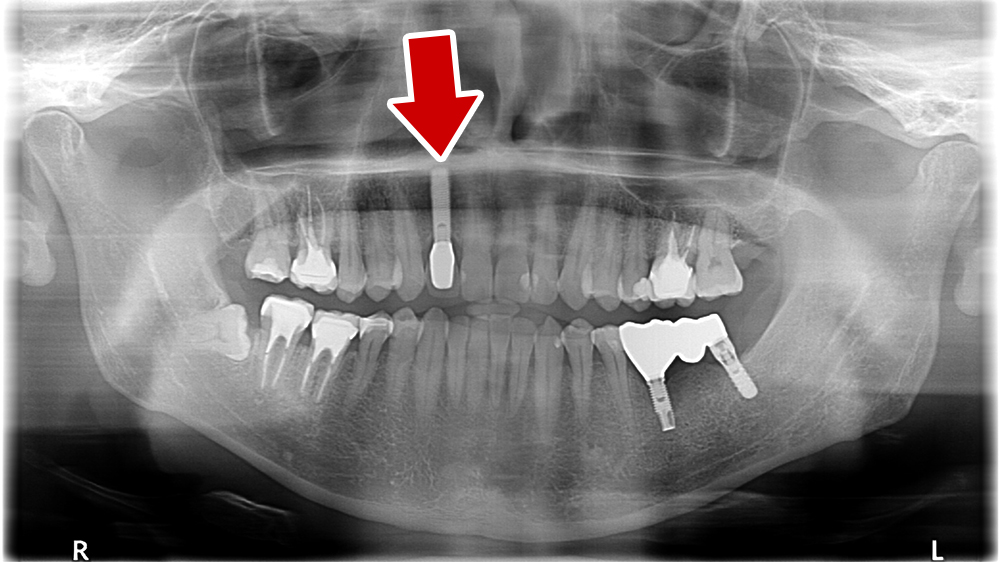

45歳 男性 医療関係者紹介

- 主訴

- 右前歯が取れた(右上2)

- 処置内容

-

1本インプラント埋入+再生療法

抜歯即時埋入⇒抜歯を行い、同時にインプラント埋入(即時埋入)

- 治療費用

- 上顎:約40万円(税込)

- 治療期間

- 約11か月

- リスク

- 上部構造物、仮歯の破折、術後の腫れ(3日)、人工歯根脱落リスクがあります